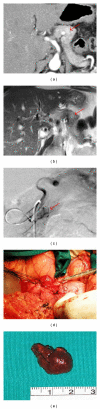

We describe an unusual case of hypoglycemic syndrome in a 69-year old woman with a proinsulin-only secreting pancreatic endocrine adenoma. The clinical history was highly suggestive of an organic hypoglycemia, with normal or relatively low insulin concentrations and elevated proinsulin levels. Magnetic resonance and computed tomography of the abdomen showed a 1 cm pancreatic nodule and multiple accessory spleens. The diagnosis was confirmed by selective angiography, showing location and vascularization of the nodule, despite no response to intra-arterial calcium. After resection, the hypoglycemic syndrome resolved. The surgical specimen was comprised of a neuroendocrine adenomatous tissue with high proinsulin immunoreactivity. Study of this unusual case of proinsulinoma underlines (i) the need to assay proinsulin in patients with hypoglycemia and normal immunoreactive insulin, (ii) the differential diagnosis in the presence of accessory spleens, (iii) the unresponsiveness to intra-arterial calcium stimulation, and (iv) the extensive evaluation needed to reach a final diagnosis.